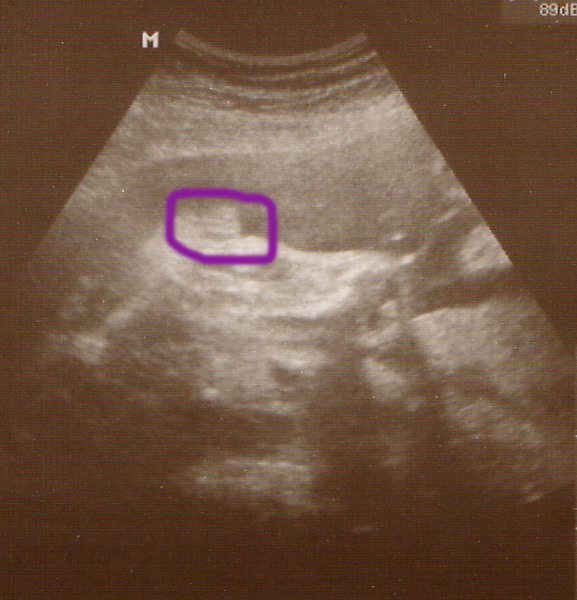

Az uh-n minden rendben volt, hallgattuk a szivhangot, vagy nem is tudom, szerintem az volt, hogy a köldökzsinórban keringett a vér és annak a hangja volt, a súlya 1262 g, szerintem az elég sok igy 28 hetesen, de nemtudom honnan tudnám ezt megnézni, meg farfekvéses még mindig a kincsem, de a doki azt mondta, hogy van még ideje megfordulni, remélem meg fog. Ééééééééééés a lényeg, hogy a doki szerint 100 %-ig biztos, hogy KISLÁNY! Hát nemtudom, én még mindig nem tudom elhinni, de kaptunk róla képet, majd otthon beszkennelem, és felteszem, hátha valaki ért hozzá?!

Mutogatta a három vonalat, és meg is kérdezte apától, hogy látja apuka?! Szegény apa mondta, hogy látja, de mit is kell nézni, és akkor elmagyarázta a doki, hogy ez a három vonal a bizonyiték a kislányra, hogy nem hazudik...